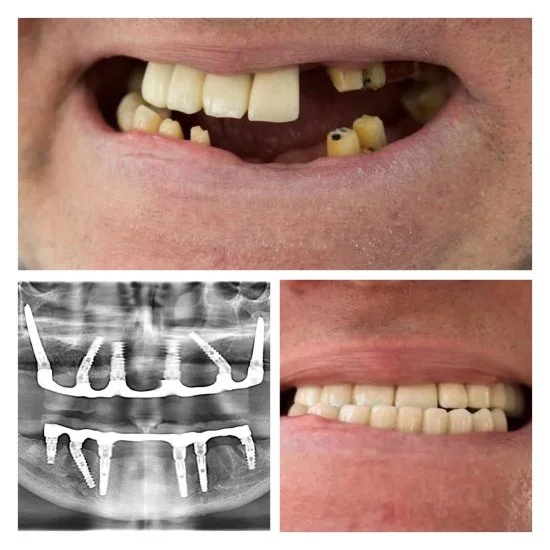

Efekty leczenia